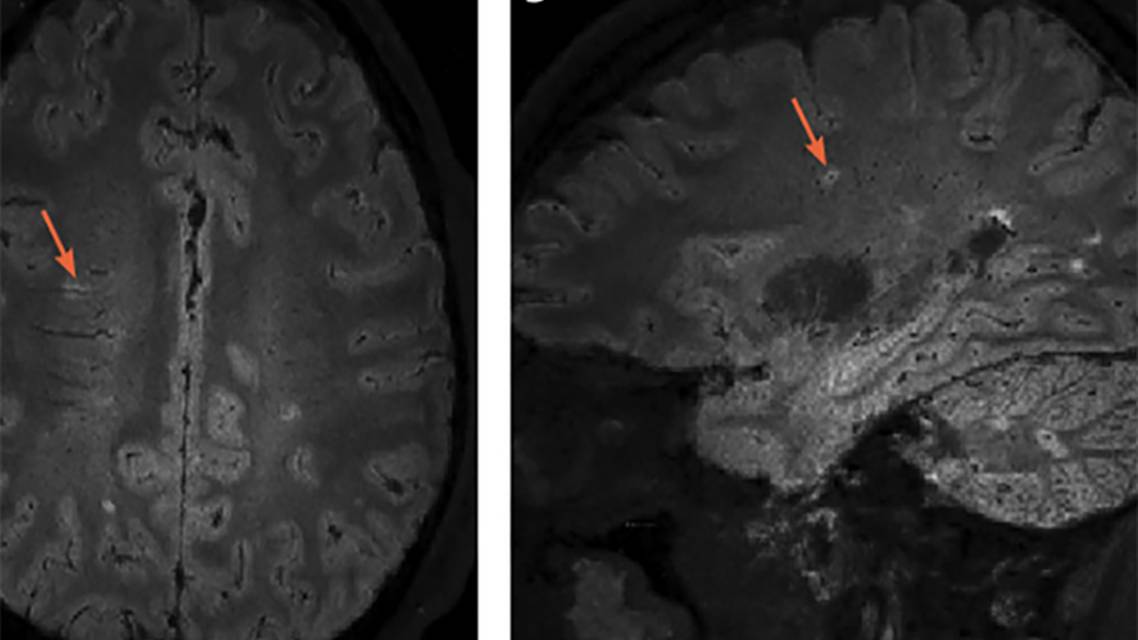

Many conditions mimic multiple sclerosis (MS) both clinically and radiologically. Despite validated diagnostic criteria,1 accurate diagnosis can be challenging. People without MS are misdiagnosed as having MS, often due to misattribution of MRI white matter lesions to MS. A novel imaging biomarker, the central vein sign (CVS), shows promise as a tool to distinguish demyelinating white matter abnormalities on MRI from lesions caused by other etiologies (eg, ischemia and migraine). Findings from pathologic specimens confirm that demyelinating lesions form around a postcapillary venule. Using susceptibility weighted MRI and standard fluid-attenuated inversion recovery (FLAIR) imaging, it is possible to determine if there is a CVS within an individual lesion (Figure). If validated, such a tool could significantly improve the accuracy of clinical diagnosis, allowing for more appropriate management of MS. Studies are underway to determine the best methods to capture and analyze this MRI finding.

The first report of a central vessel in MS lesions came from manuscripts prepared between 1829 and 1842 on the histology of MS plaques by anatomist Jean Cruveilhier.5 It was not until 150 years later, in 2008, that the first in vivo demonstration of these vessels was available with high-field MRI.6 The North American Imaging in Multiple Sclerosis (NAIMS) Cooperative provided a standardized definition for the CVS in their 2016 consensus statement (Table).7 The statement defined the CVS as a thin hypointense line or small dot positioned centrally in a lesion larger than 3 mm. The CVS is best visualized on susceptibility-weighted images coregistered to T2-images (eg, the FLAIR* technique) (Figure).